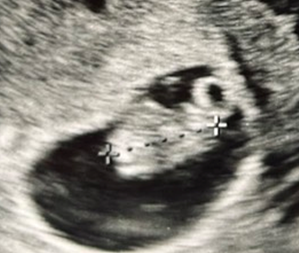

こちらが今回のエコー写真です。

すごく気になったのが、「CRL 14.4mm」の文字。

前回不妊治療クリニック卒業の際に測ったときのCRLは13.2mmでした。

この1週間で1mmしか大きくなっていない。

また、先ほど載せたエコー写真には

「CRL 14.4mm GA 8w1d」

という表示が出ていました。

つまり、この産院で使用しているエコー機械の基準では、8週1日相当の問題ないサイズと判断されていた、ということになります。

対して今回は丸っこく胎芽が見え、卵黄嚢らしきものも楕円形に見えます。

明らかに撮影している角度が違う気がする